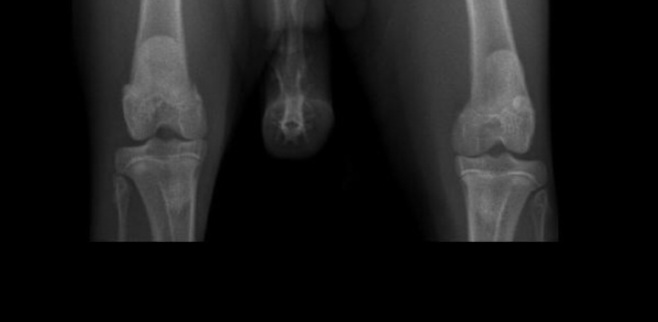

Xavier pl knieën 👍

Afbeelding – 17,4 KB

169 downloads

Download